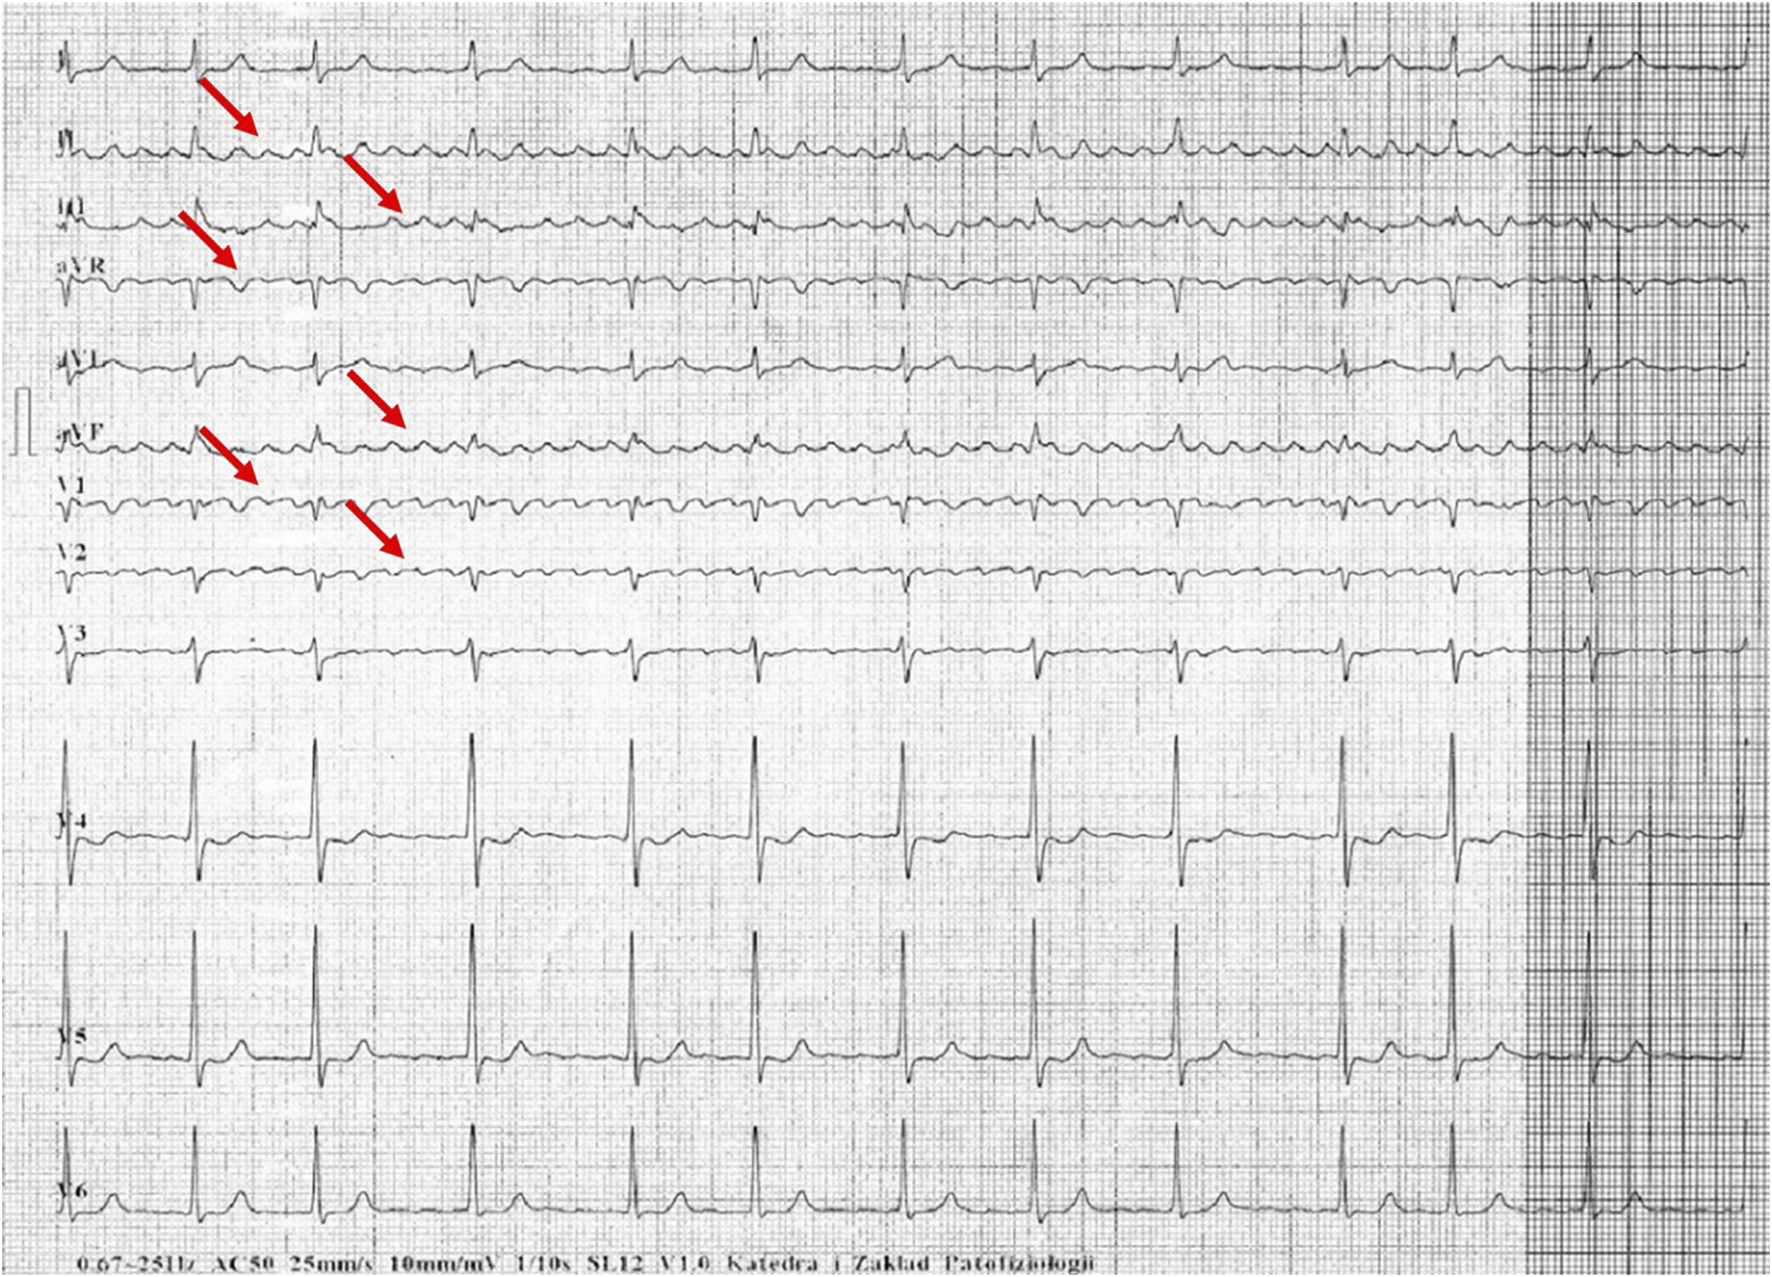

Figures 1–5 present a sample of ECGs incorrectly interpreted by the device. There are cases of pathologies commonly identified by clinicians. In Figure 1, we identified the dual-chamber pacing with a dual response (DDD) stimulation interpreted as atrial fibrillation and RBBB, so in this case, we have both overinterpretation and failure of recognition. A similar situation is presented in Figure 2, where we found the lack of atrial fibrillation diagnosis and at the same time overinterpretation with type 1 and 2 atrioventricular block. In Figure 3, the situation is presented where, instead of DDD pacing, LBBB and the atrial rhythm were proposed. Moreover, in Figure 4, the compensatory pause after premature ventricular beats was overinterpreted as atrioventricular Mobitz type II block. Finally, in Figure 5, we again identified the lack of proper diagnosis of the first-degree atrioventricular block, together with the overinterpretation of atrial fibrillation.

FIGURE 1

Example of incorrect interpretation by the device: Male, 85 years old. The rhythm was described as atrial flutter with a complete right bundle branch block (25 mm/s, 10 mm/mV). The real diagnosis is dual chamber pacing.